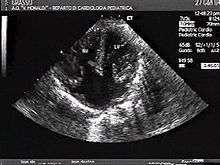

Atrioventricular canal defect

Atrioventricular canal defect may be divided into partial or complete forms. In the partial form, openings between the left and right atria and improper formation of the mitral valve exist. In the complete form, there is free movement in all chambers because there is a large hole where the atria and ventricles meet, and instead of there being two valves there is one common valve.[4]